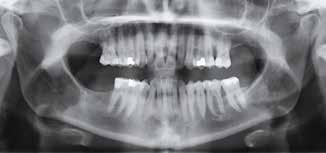

Der ses anterior trangstilling i begge kæber og overerupterede 1+1 og 2,1-1,2, hvilket resulterer i dybt bid med 2- tæt på ganepåbidning. Der er normale sidetandsrelationer, men der ses 5 mm horisontalt overbid (HOB) og 7 mm vertikalt

overbid (VOB). Papillen mellem 1+1 er betydeligt reduceret pga. fæstetab, og de mesialt kippede 1+1 har resulteret i en ”dark triangle”. Den facioorale funktion er for nuværende i.a. Panoramarøntgen (Fig. 1, I) viser marginalt knogletab i begge kæber og fravær af 8,7+7,8 og 8,7-8.